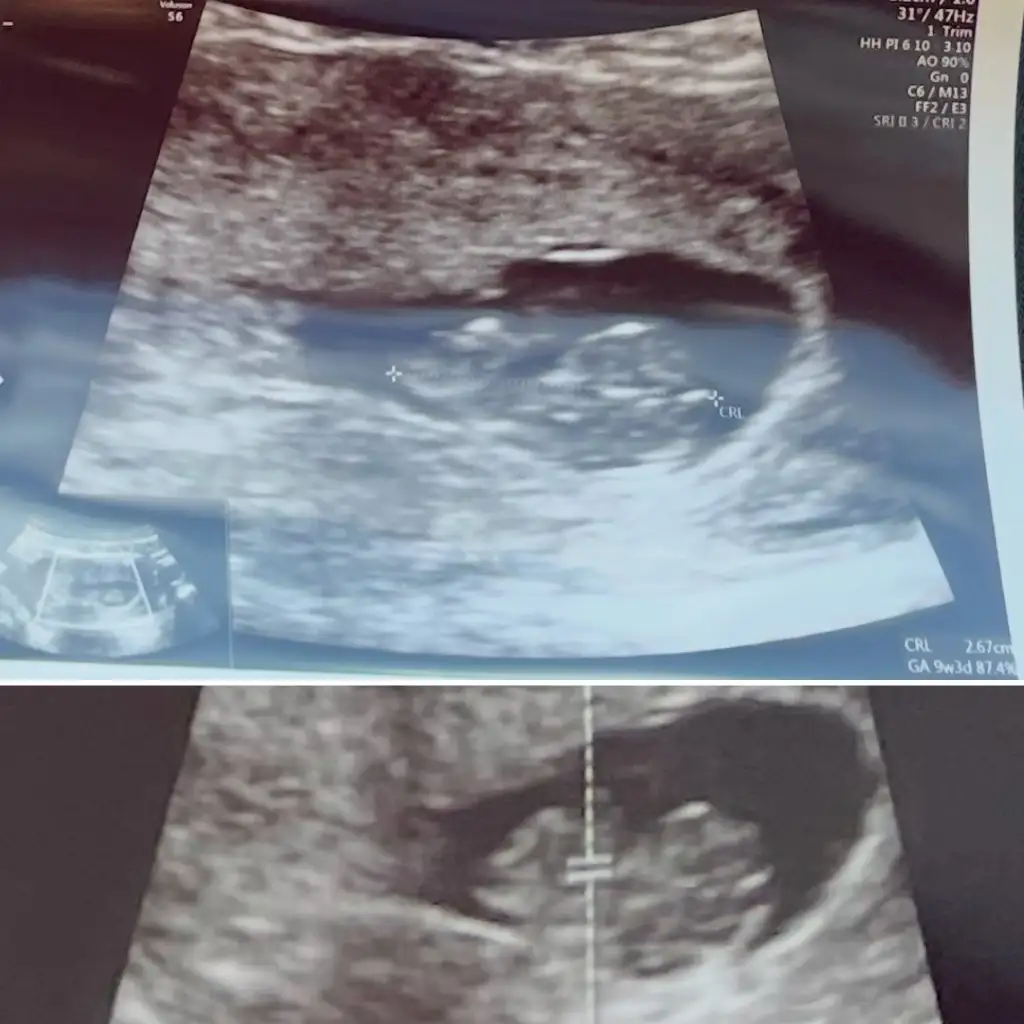

Benimde 5+2 bakabilir misiniz vajinal ultrason. Ayy çok heyecanlıyım

Sizinde erkek sanırım 🥹kaç haftalık bende haftaya cuma gidicem kalp atışı için bugün 6+2 benim keseye de gitmedim hiç bakalım benim ultrason kağıdı nasıl

Burda 8+5gunluk .. inşallah hayırlısı kalp atışında duyarsiniz kucaginizada alırsınız birde erkek olduğunu nerden anladinz